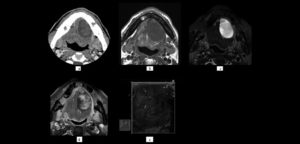

En los pacientes desdentados, que requieren una prótesis completa ya sea convencional o implanto soportada, los dientes artificiales se colocan en la prótesis completa por